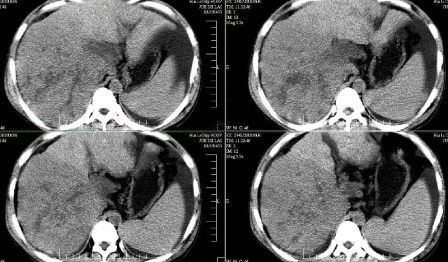

标题: CT13930:M,33岁,腹胀、腹痛10天余。 [打印本页]

标题: CT13930:M,33岁,腹胀、腹痛10天余。

右上腹压痛,肝大,质硬。腹水征。ct:肝右叶(后段)低密度影,性质待定。

肝硬化、腹水,肝右叶低密度首先考虑肝癌可能,左叶低密度不除外转移可能。建议增强检查。

肝硬化、大量腹水,肝右叶巨大肿块,境界欠清,中间见不规则低密度坏死区,考虑肝癌应该问题不大,至于肝左叶低密度灶是否转移应该意义不是很大了,慎重起见还是建议增强扫描。